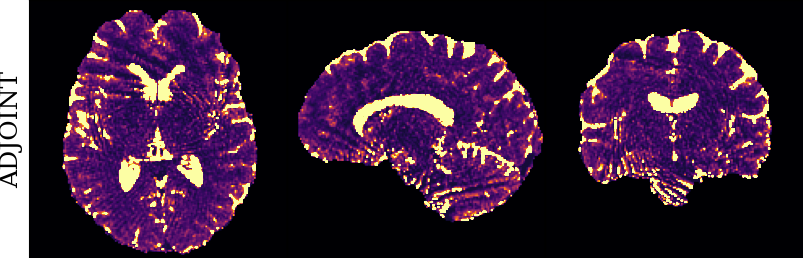

To monitor performance progress, we mapped TSMI to Q-Maps every five epochs. To mitigate the lengthy processing times associated with Dictionary Matching, we implemented a fully connected network to directly map TSMI to Q-Maps [5], significantly reducing processing time. However, for the final assessment, we employed DM on all techniques at the conclusion of the training process (epoch 500). We report in Table 1 the Mean Average Percentage Error (MAPE) of T1/T2 maps, and Peak Signal-to-Noise Ratio (PSNR) and Structural Similarity (SSIM) Index for T1/T2 and normalised PD. To accompany these metrics we also offer in Fig. 2 the reconstructed T1 and T2 maps for the different approaches.

The training and validation loss (Fig. 1) served as valuable guides for architecture and training design. To demonstrate this, we selected a subset of experiments in which we kept certain variables fixed and only modified the one under inspection. From Fig. 1 (a)-(d), MAPEs curves show there is a clear setting with the preferred performance. Specifically, from Fig. 1a, it is evident that using DRUNet yields a clear improvement over the original architecture. This could be attributed to the utilisation of residual units in addition to other architecture differences, such as the choice of upsampling operator (transpose convolution for DRUNet and trilinear for DIP). The choice of input (Fig. 1b) demonstrated a consistent pattern among the tested options, with low rank (conjugate gradient) initialiser marginally outperforming the others. Fig. 1cshows that by epoch 100, stochastic approaches exhibit lower reconstruction errors compared to non-stochastic methods. For example, adaptive LR with stochastic training yields a combined MAPE of 61.40% (17.09% T1 and 44.31% T2) vs. 213.69% (35.50% T1 and 178.19% T2) for the non-stochastic method. This fast convergence is due to adaptive LR and stochastic updates across coils. Despite similar execution times ( 34 min for stochastic with adaptive LR vs. 32 min for non-stochastic with fixed LR), the rapid error reduction makes StoDIP more attractive for training.. To assess the early stopping of DIP models, a key element, we present Fig. 1d. The original work by Ulyanov et al. [21] used 2k iterations, while Hamilton et al. [12] used 30k. In contrast, our settings show StoDIP achieving competitive performance in under 500 epochs (4k iterations) on the entire volume. However, StoDIP can overfit to k-space measurements, affecting reconstruction accuracy, and thus the iteration at which it stops could have a greater impact. We show that adding a spatial penalty term addresses overfitting and instabilities. This is supported by the maps in Fig.2, supplementary material Figures 1-3, and metrics in Table 1. StoDIP reconstructions lack aliasing artifacts, and the TV regularizer (StoDIP + TV) further improves Q-Map reconstruction by reducing checkerboard artifacts observed in StoDIP outputs alone.